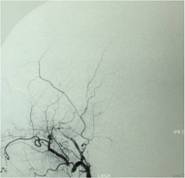

经查体,神经外六科吴杰主任诊断为:左侧蝶骨嵴占位性病变,考虑脑膜瘤可能性大。之后黄女士完善了相关检查,颅脑CT及CTA检查提示:左侧中颅窝底巨大占位病变,其内血管丰富,临近左侧大脑中动脉明显受压向上移位,考虑脑膜瘤;颅脑磁共振提示:左侧前中颅窝底巨大占位性病变,考虑脑膜瘤。介入栓塞提示:肿瘤主要由左侧脑膜中动脉额支、少量由左侧眼动脉脑膜支参与供血。

经家属同意后,医生决定栓塞肿瘤近端的供血动脉,并于当天行左侧中颅窝占位病变切除术;术中可见肿瘤灰红色,有假包膜,分块切除肿瘤;由于术前行介入栓塞,术中可见血供明显减少,且出血少,左侧大脑中动脉及左侧大脑前动脉被肿瘤压迫移位,医生给予保护后将肿瘤全切除。术后黄女士恢复顺利,已痊愈出院。病理结果显示:脑膜瘤,合体细胞型,WHO I级。

DSA显示栓塞前肿瘤主要由左侧脑膜中动脉额支供血,栓塞后肿瘤血供明显减少